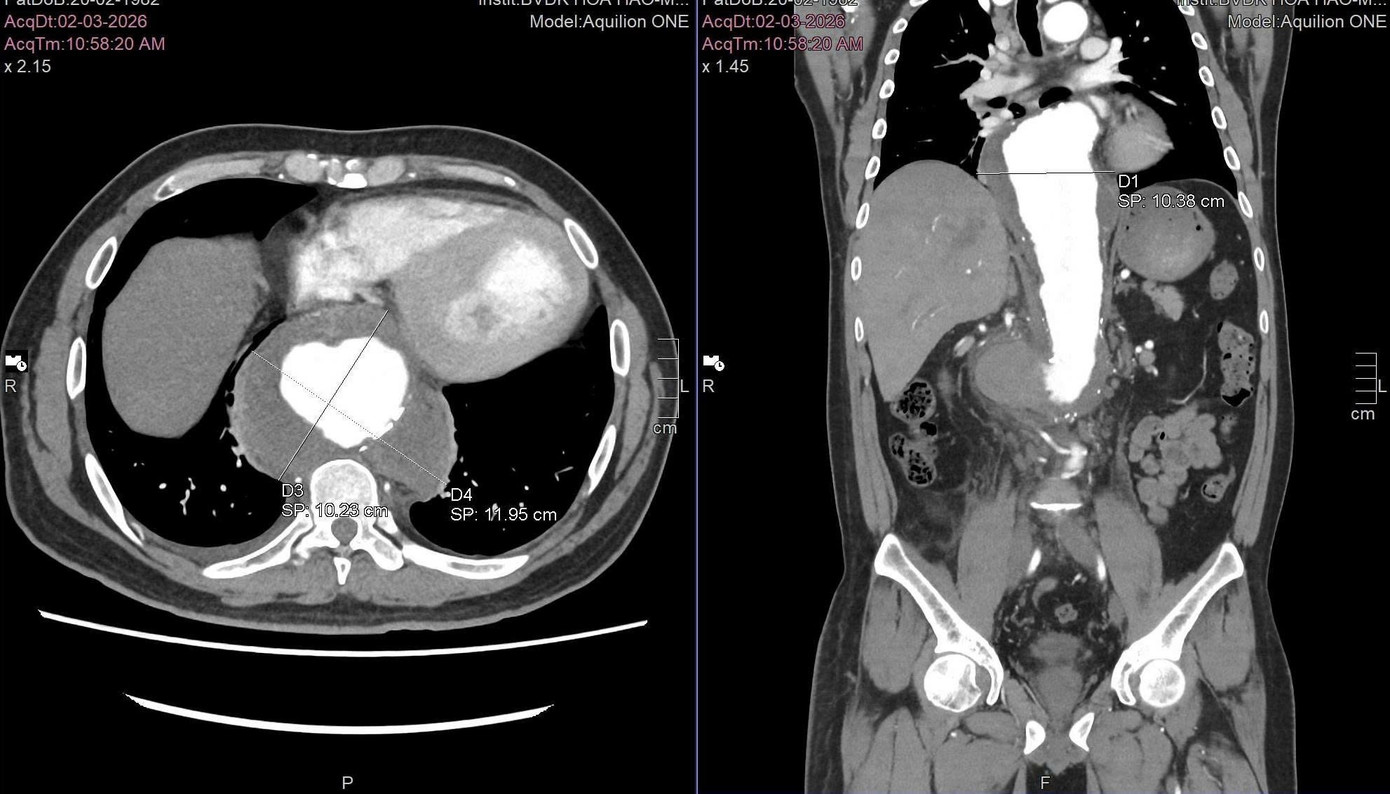

Ngày 24/3, ThS.BS Đặng Văn Sô Đa, khoa Ngoại Tổng hợp, Bệnh viện Đa khoa Quốc tế S.I.S Cần Thơ cho biết, bệnh nhân L.Q.L. (44 tuổi, ngụ tại Cần Thơ) nhập viện trong tình trạng đau bụng dữ dội, mặt tái, vã mồ hôi. Kết quả chụp CT mạch máu cho thấy túi phình động mạch chủ ngực – bụng đã vỡ, kèm khối máu tụ lớn sau phúc mạc, đường kính lên đến 11cm. Đây là dạng tổn thương có nguy cơ tử vong cực cao do mất máu cấp.

Các bác sĩ xác định, túi phình động mạch chủ ngực - bụng bị vỡ khiến người bệnh rơi vào nguy kịch